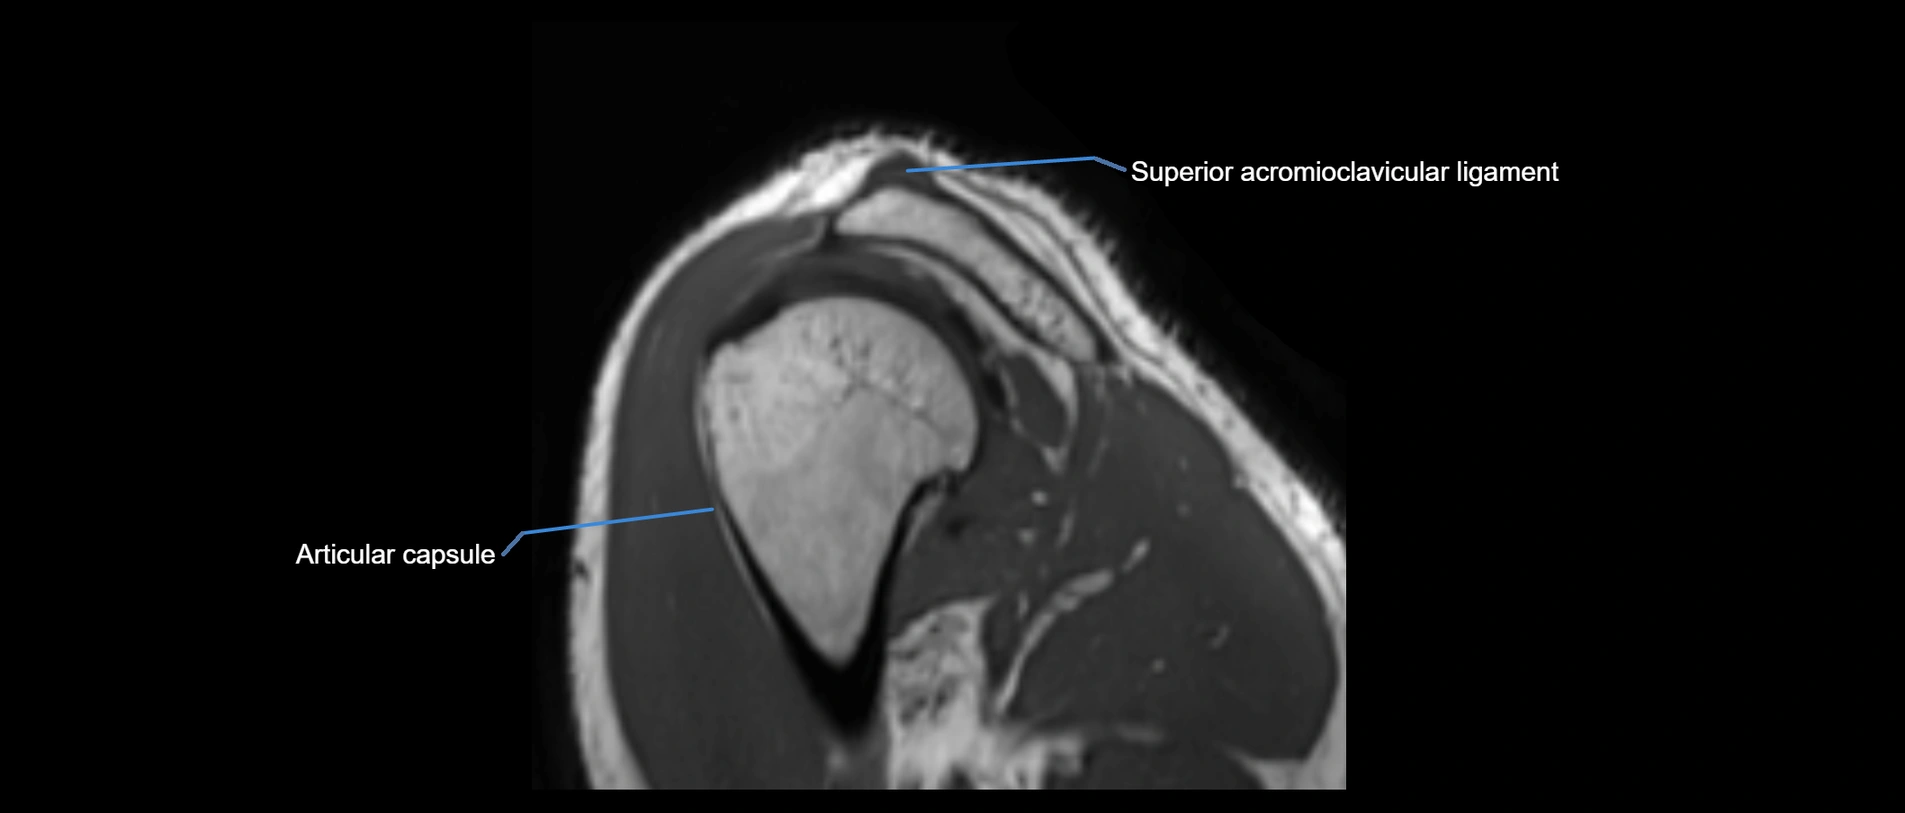

CT image

image